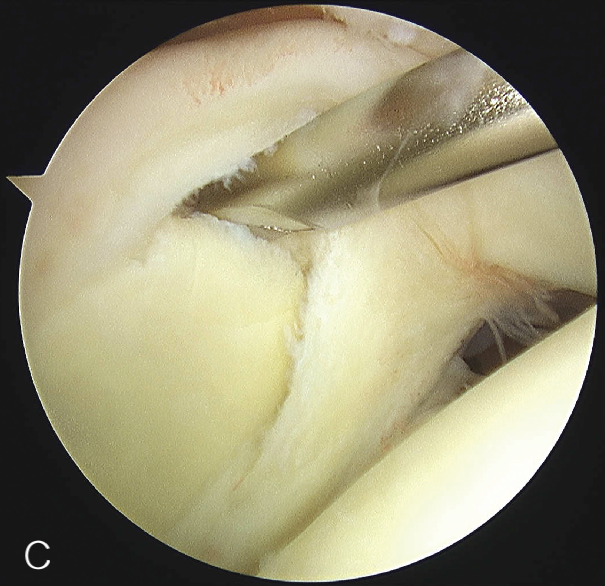

修复处准备